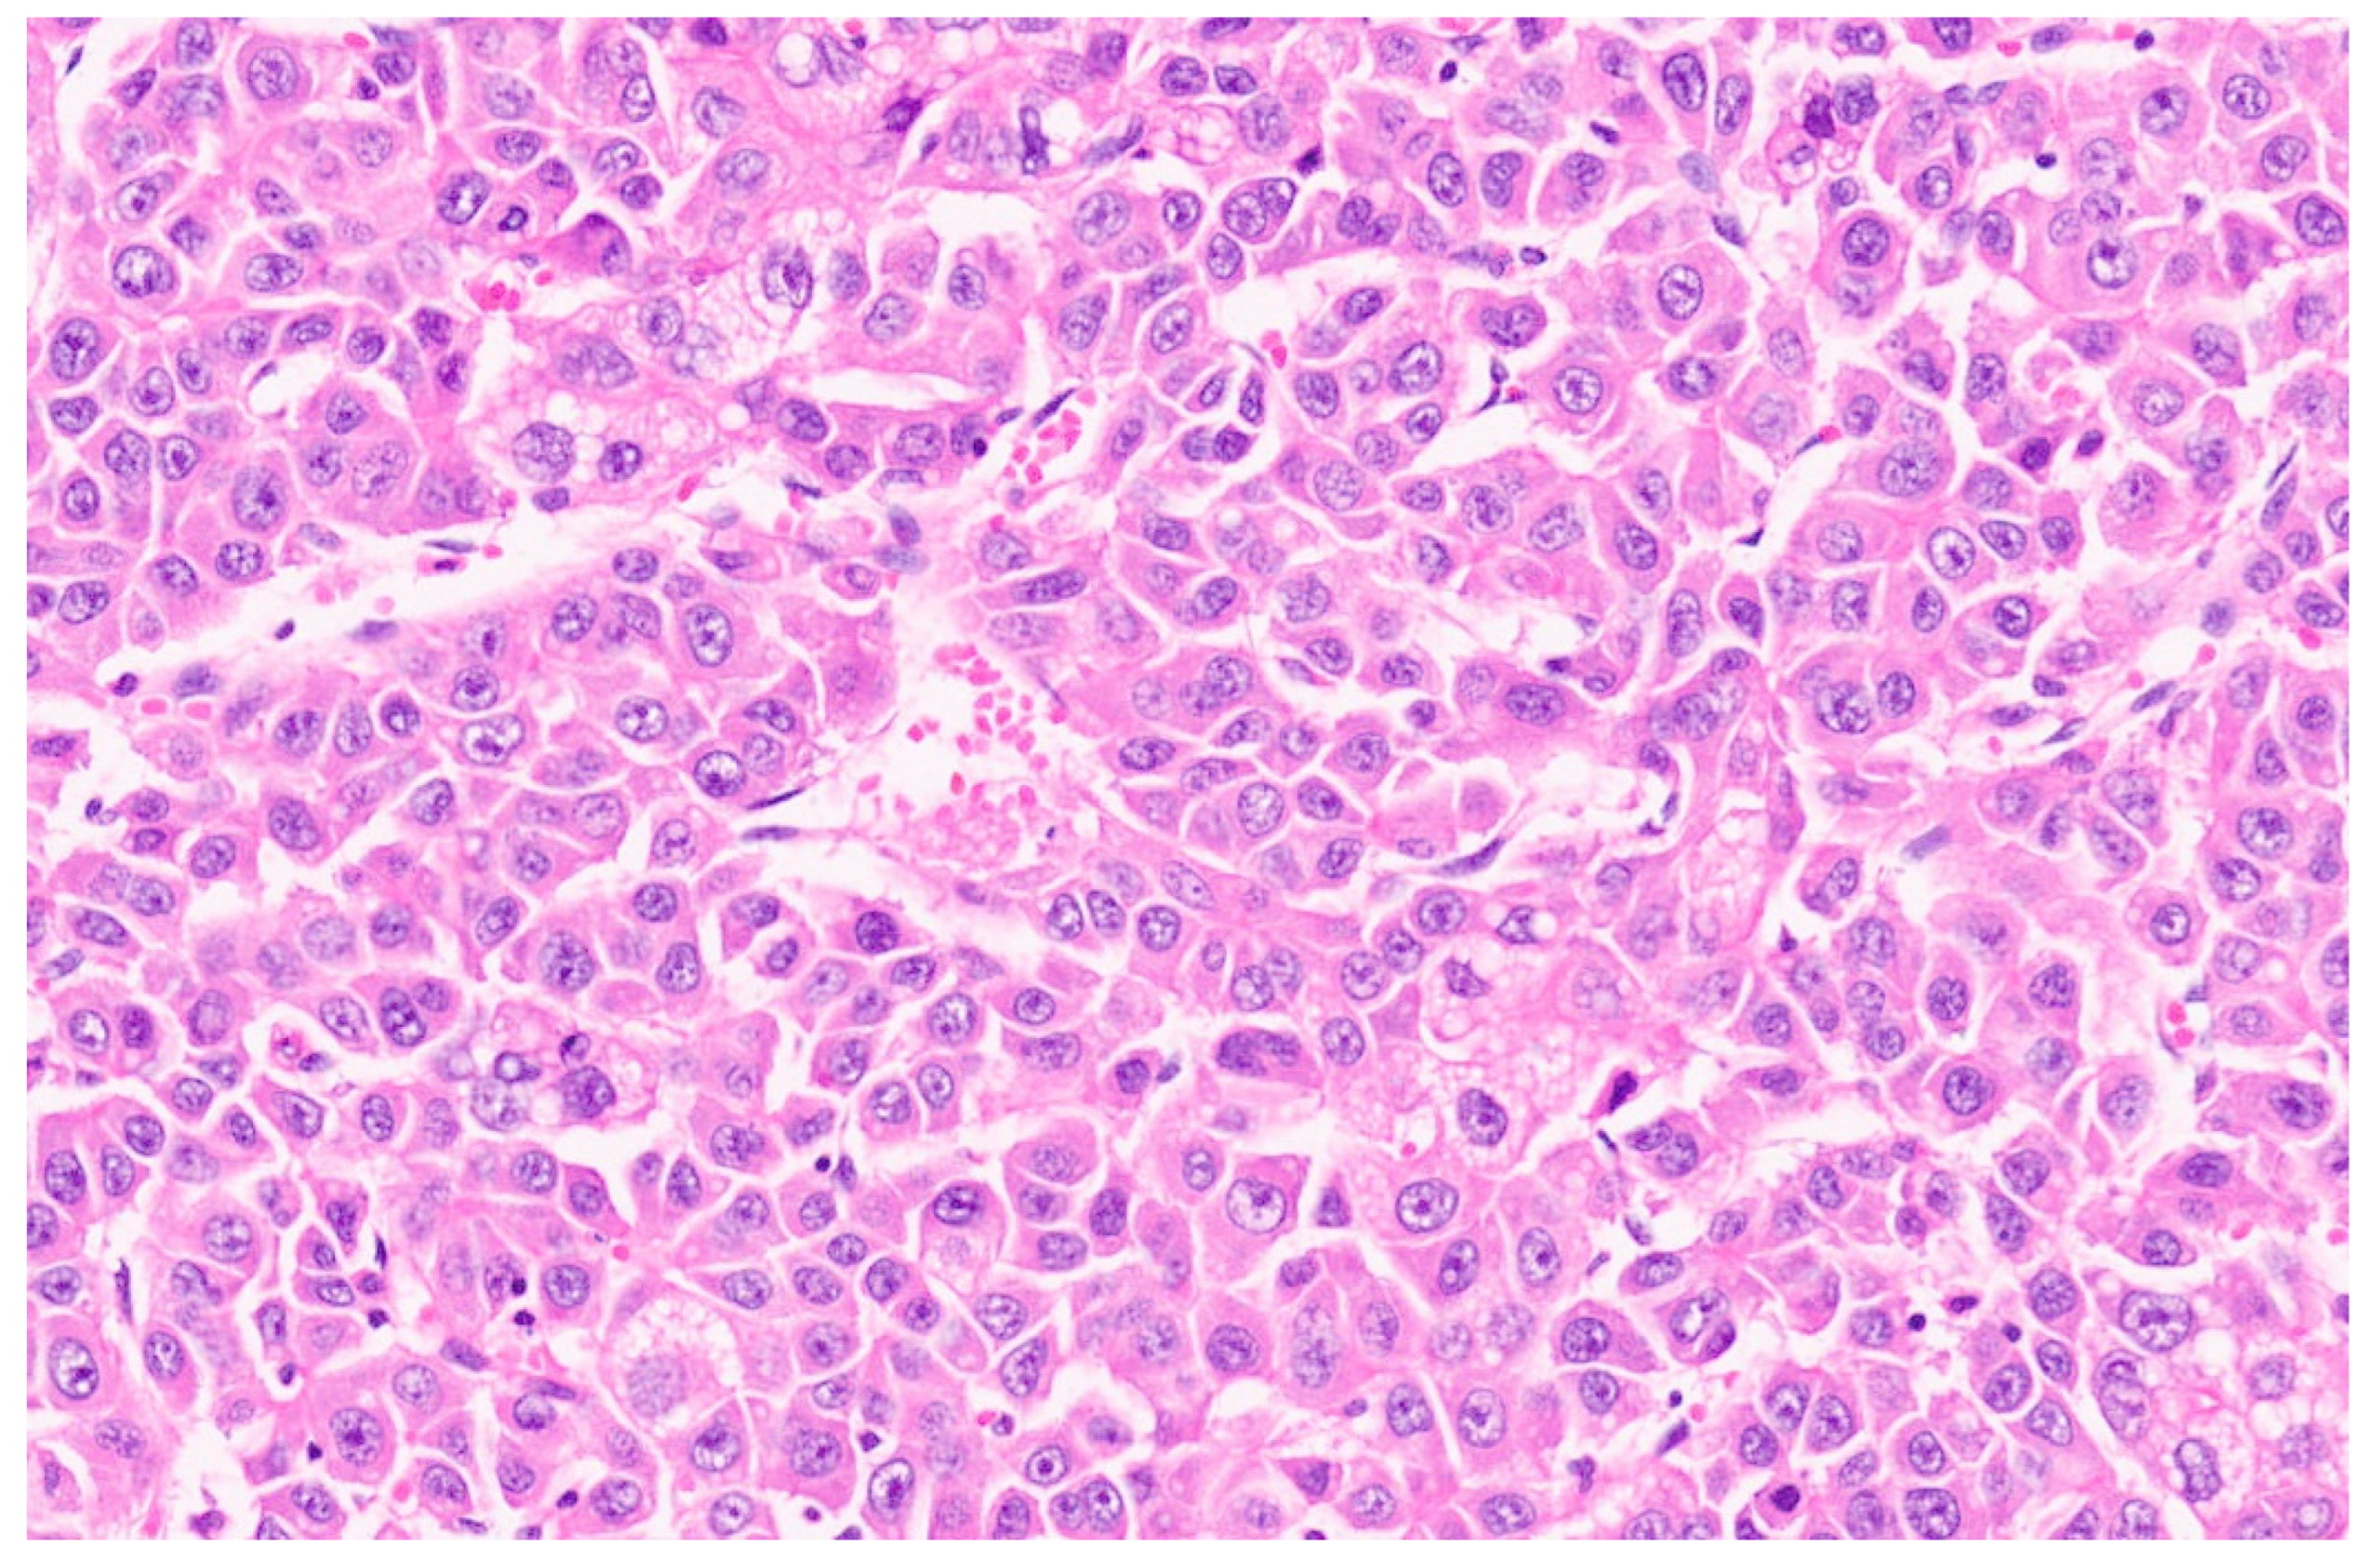

16.3. Pathology

| Histopathology | Well Differentiated | Moderately Differentiated | Poorly Differentiated |

|---|---|---|---|

| Arrangement | Trabeculae that are at least 3 cells thick and lined by sinusoids, pseudoacinar arrangement | Trabeculae that are 15–20 cells thick lined by sinusoids, pseudoacinar arrangement | Sheets or nests of cells not resembling hepatocytes. |

| Cells and nuclei | Resemble hepatocytes with mild nuclear pleomorphism, centrally placed round nuclei, and abundant cytoplasm | Moderate nuclear pleomorphism, large nuclei with prominent nucleoli and intranuclear inclusions, abundant cytoplasm. | High N/C ratio, nuclear pleomorphism, prominent nucleoli and intranuclear inclusions, numerous mitosis |

| Necrosis | Usually absent | May be seen | Present |

| Immunohistochemistry | Variable glypican 3 and glutamine synthetase levels. Negative for β-catenin nuclear staining | Glypican 3 and glutamine synthetase are positive in 50% of cases, β-catenin is variable | Glypican 3 and glutamine synthetase |